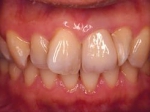

インセラム(オールセラミック)症例①

治療前治療前インセラム(オールセラミック)冠による修復。 主訴は前歯が汚い 金属を使わないオールセラミックでの治療を勧めた。 術前 治療後治療後術後